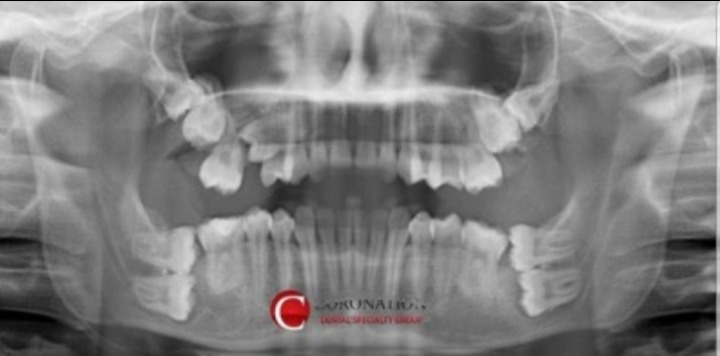

저주받은 사랑니 레전드